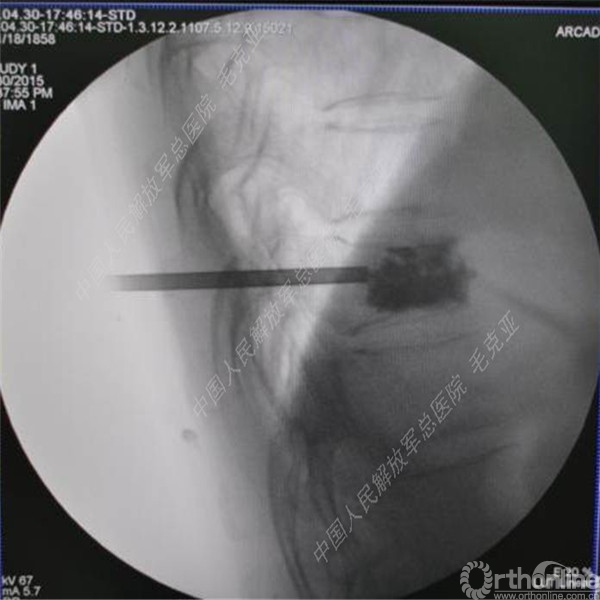

导语:随着社会老龄化的不断加速,骨质疏松性椎体压缩骨折作为一种普遍存在的老年骨科疾病已经成为现今骨科界的一个热点话题。传统的保守疗法治疗效果不佳,而现有的椎体增强技术又具有多种风险和缺陷。针对这种现状,中国人民解放军总医院毛克亚教授提供了一种新的解决方法。